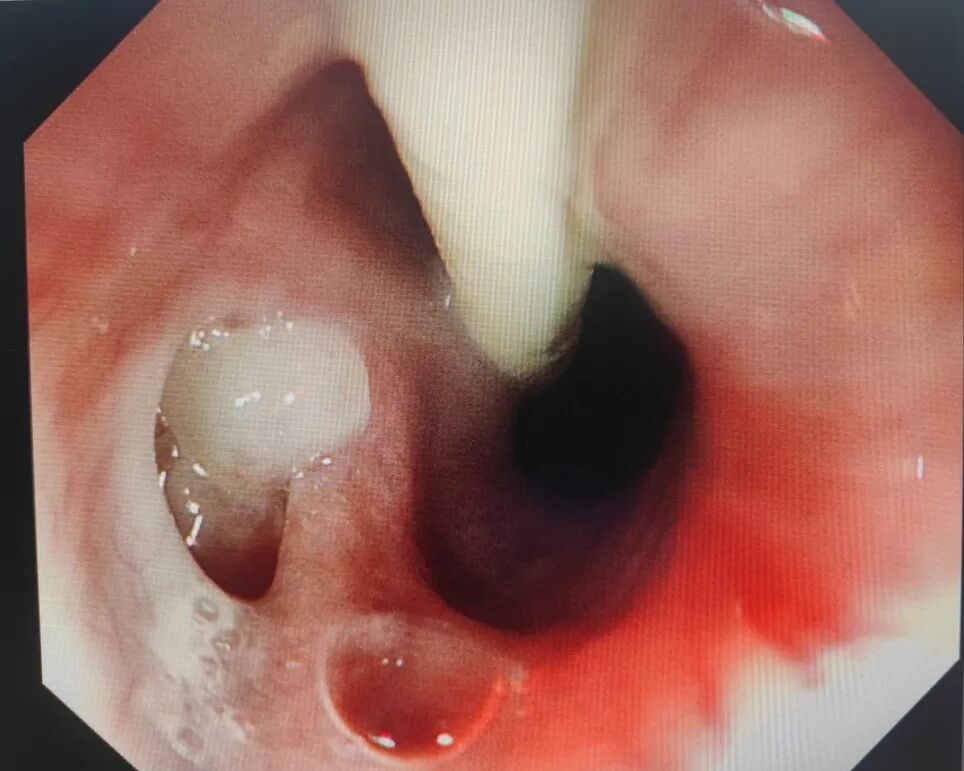

术后

术后第二天行上消化道造影提示瘘口完全被夹闭。